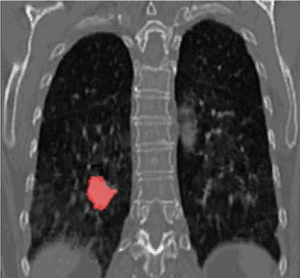

Bij de bestraling van bepaalde gebieden van de long, houden we ook rekening met de ademhaling. We monitoren jou ademhaling waardoor we de beweging van de tumor in beeld kunnen brengen.

Je kunt hierbij gewoon normaal ademhalen. We maken een unieke berekening op jou ademhaling zodat je tijdens de bestraling op een normale manier kan ademhalen.